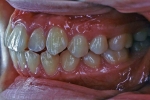

| 治療中